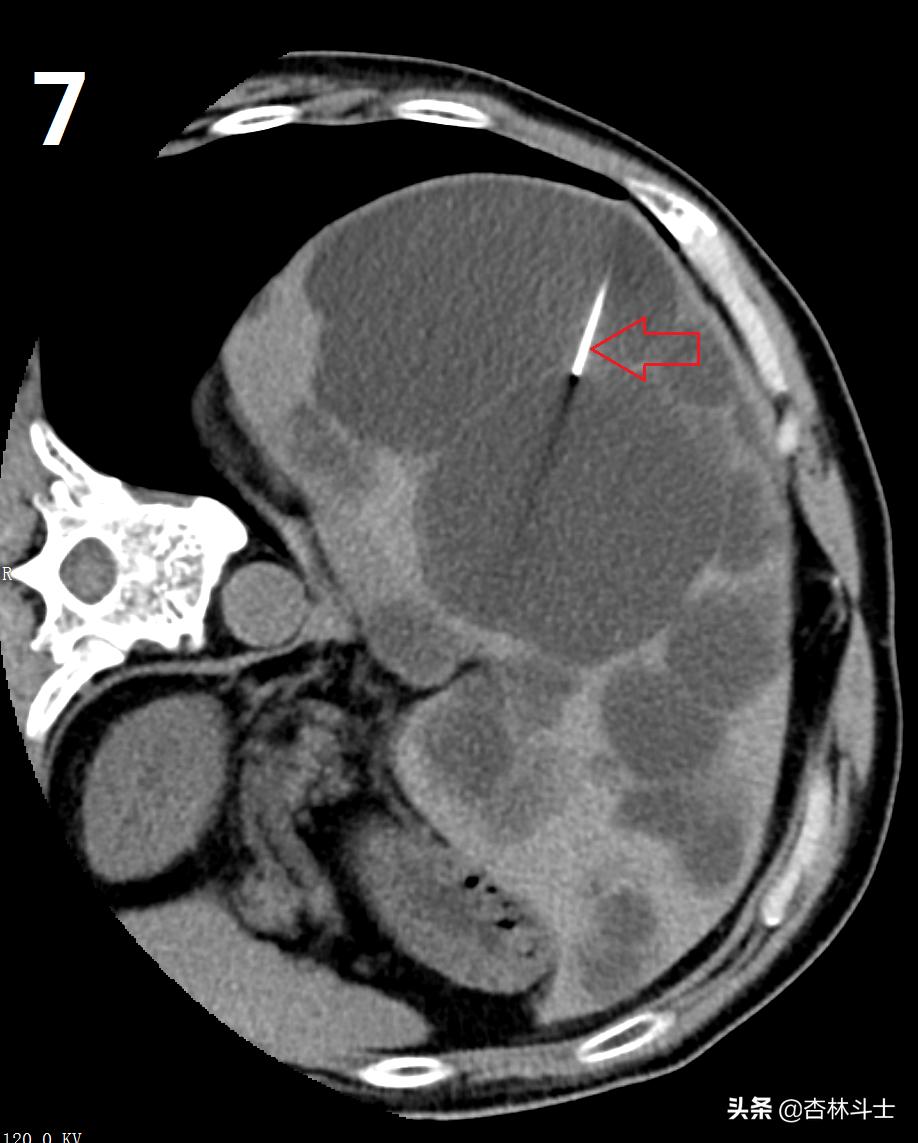

图7-8-9为上次做微创手术术中部分图像,红箭头所示为超细酒精抽吸硬化针,直径约0.79㎜,图9中五角星为囊腔内囊液被抽吸干净,最后一幅图是抽出来的黄色清澈囊液。同时被注入的无水酒精所代替。